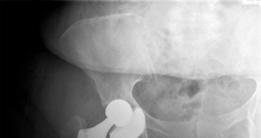

Reduction and Closure

The hip is reduced by applying axial traction and internally rotating the limb. Fluoroscopy is used to assess leg length (comparing the teardrop-to-lesser trochanter distance bilaterally) and offset. Clinical stability is tested by taking the hip through a full range of motion, specifically checking for anterior impingement in extension and external rotation.

Clinical & Radiographic Imaging